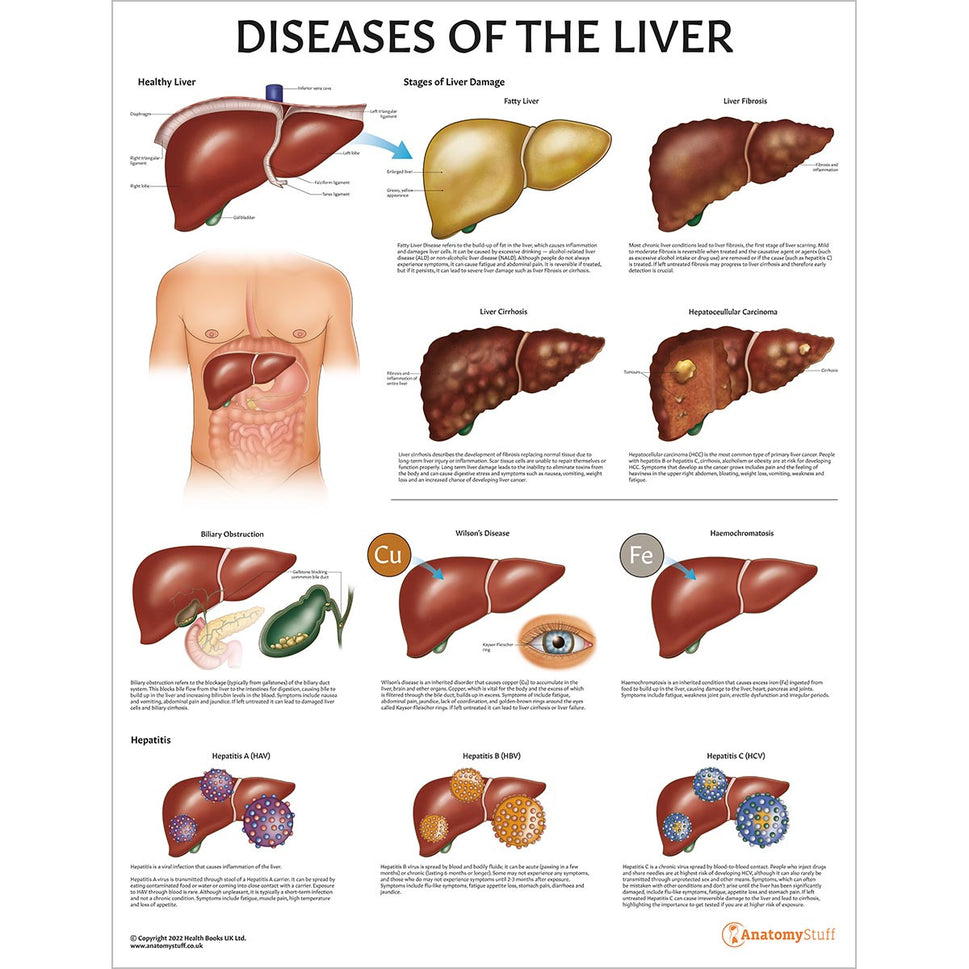

Enhance medical education with our collection of digestive system anatomical models including the stomach, liver, gallbladder, pancreas & colon models. Discover the anatomy of healthy organs as well as common gastrointestinal diseases such as stomach ulcers, gallstones and liver cirrhosis. Our digestive system anatomy posters are ideal for study and patient education.

At AnatomyStuff we stock a diverse range of digestive system anatomical models to suit your training needs. From budget models and affordable medical education posters to highly advanced 3D printed bowel models, you can transform medical training and patient education. As well as our own exclusive collection, we are proud resellers of 3B Scientific, Anatomy Lab, Denoyer-Geppert Science Company, ESP Models, Erler Zimmer and GPI Anatomicals. Explore our exclusive collection of digestive system anatomy charts, posters, fine art prints and digital anatomy study guides. Discover the anatomy of key organs like the liver, stomach, pancreas and bowel as well as the pathophysiology of common conditions like peptic ulcer disease, coeliac disease, IBD and much more. We have anatomy posters suitable for school children all the way up to medical degree level. From a liver anatomy poster to a digital study guide all about common GI disorders, find exactly what you need right here to enhance medical training and patient education.